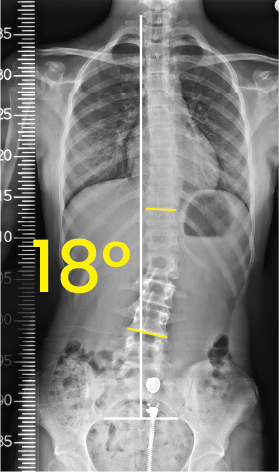

Toraks ve karın bölgesinin X-ray görüntüsü, omurga 18 derece lateral skolyoz ile hafif eğrilmiş.Göğüs bölgesini gösteren röntgen filmi, belde 7 derece eğrilik ölçümü ile omurga hizalarında metal işaretleyiciler.

Torakal omurgada sağa doğru 18 derece eğriliği gösteren röntgen görüntüsü.Toraks röntgeninde orta çizgiye göre 11 derece eğimli omurga görünümü.